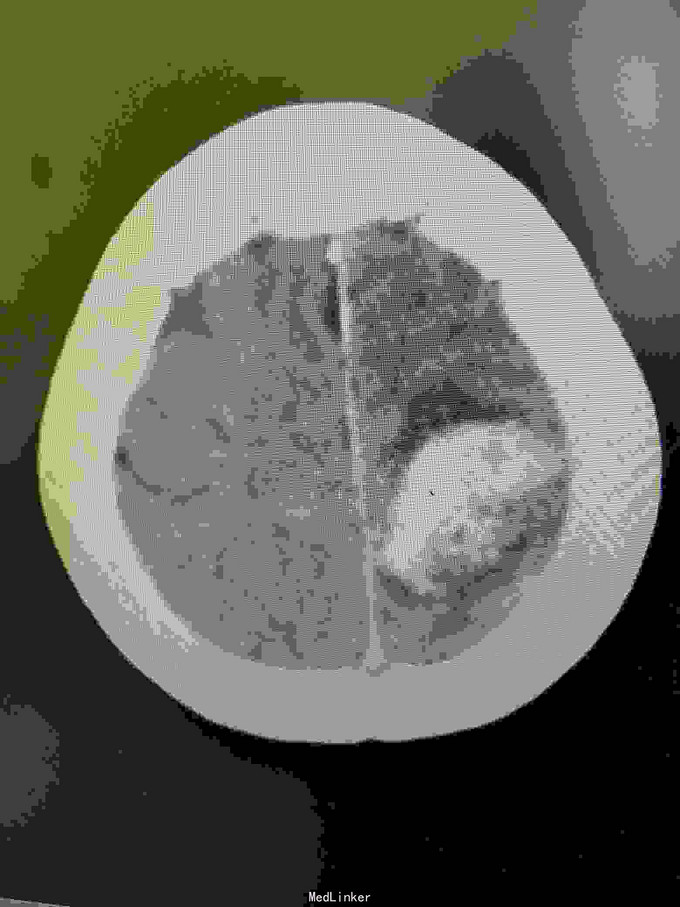

女性,65岁。入院前半年查出AvM,半年后出血入院。

左枕顶区AVM。 左大脑后及左大脑前供血,深部静脉回流。

AVM治疗如能栓塞治疗创伤较小,手术切除虽较完全,但损伤是不可突视的问题。